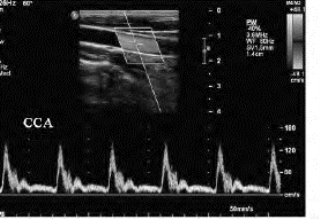

1.26.3三、正常血管

1.26.4四、动脉闭塞性疾病